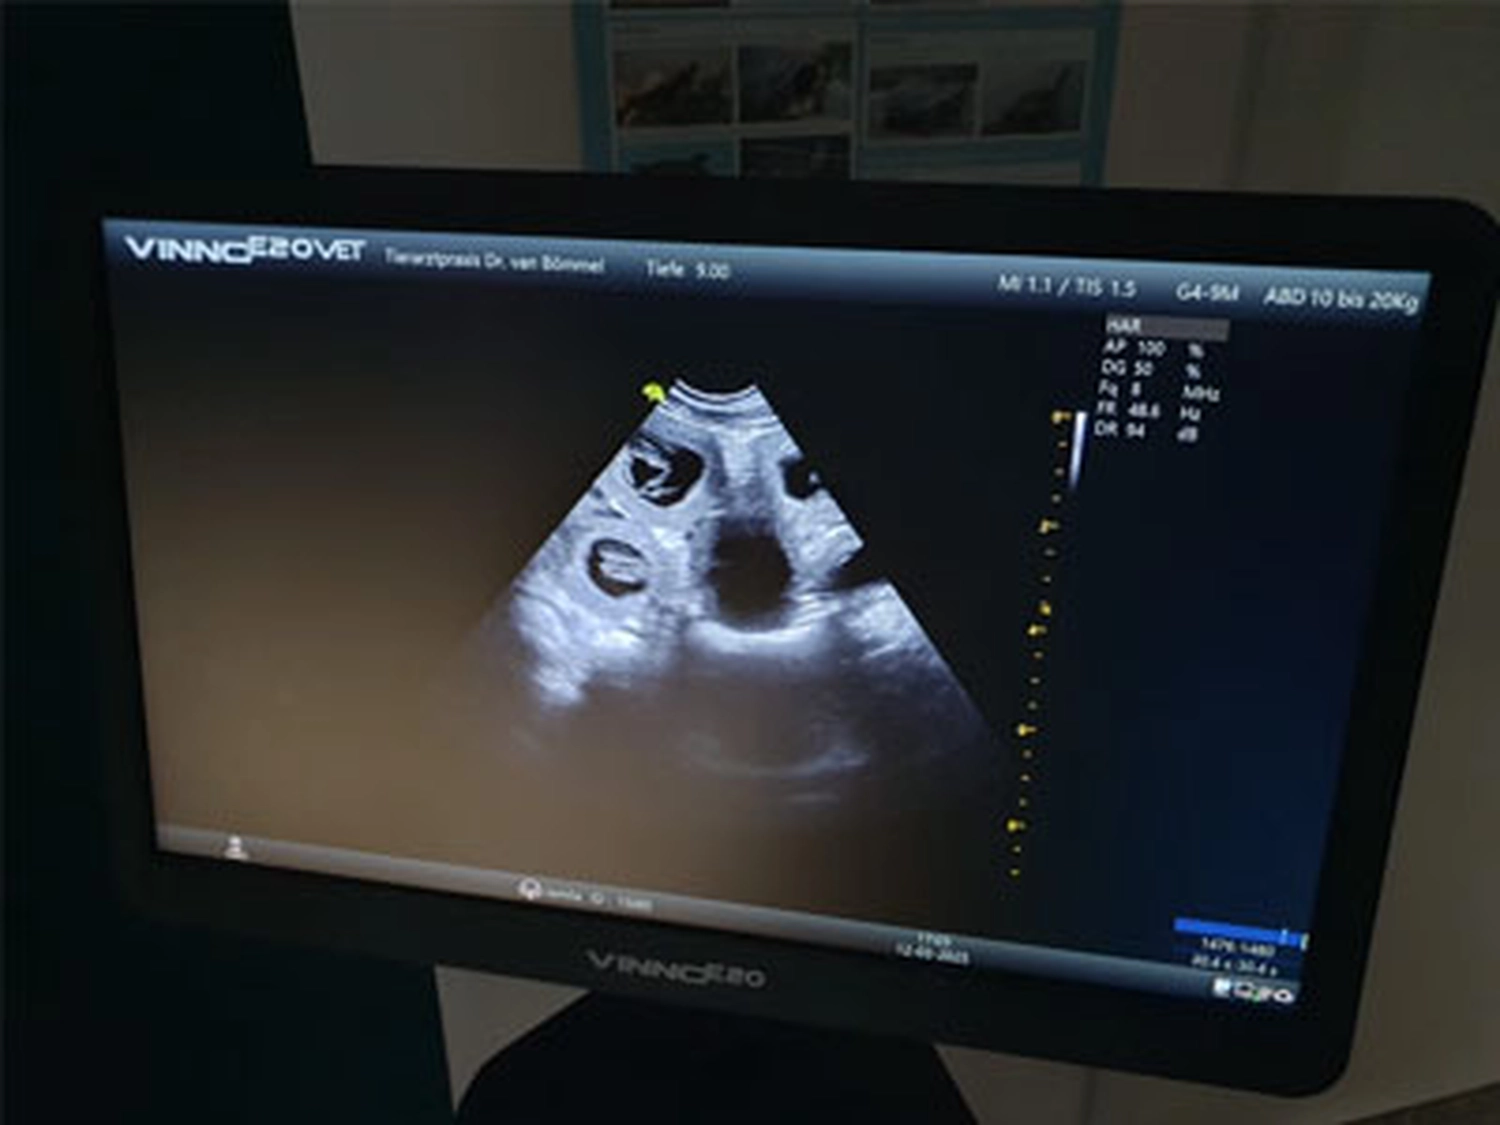

Wir freuen uns riesig über das positive Ultraschalbild von unserem N - Wurf. Katniss ist tragend und wir erwarten die Welpen Ende Januar.